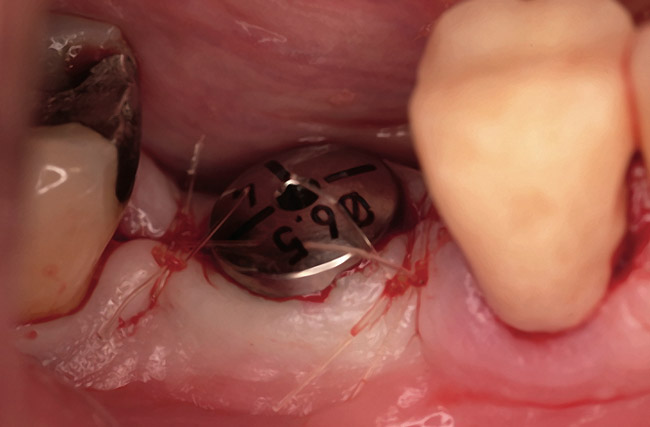

Fifteen weeks after the first procedure, the site was reopened to perform implant placement. Flap reflection revealed excellent and complete bone reformation (Figure 3). The implant osteotomy preparation was initialized with the harvest of an approximate 5-mm trephine core. The trephine had an internal diameter of 2 mm and an outer diameter of 2.7 mm. The completion of implant placement was performed according to the manufacturer's guidelines, resulting in the delivery of a 5-mm x 11-mm implant with primary stability. Because of excellent subjective stability, a transmucosal healing was chosen, with placement of a healing cap and a nonsubmerged closure (Figure 4). Qualitative histology demonstrated lamellar bone without evidence of the ACS carrier. Restorative therapy commenced approximately 4 months after implant placement. Delivery of the definitive prosthesis, consisting of a gold custom abutment and cement-retained crown, occurred at 5 months following implant placement surgery and 8.5 months after extraction and augmentation (Figure 5).